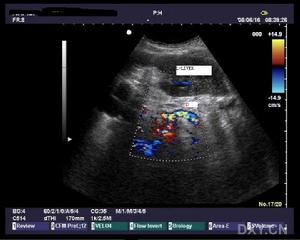

膽總管結石B超診斷檢查

3.B型超音波檢查雖然價廉無創,對膽囊結石的準確率達98%,但因受十二指腸等空腔臟器的影響,對膽總管結石的準確率僅為50%左右,特別對十二指腸後段膽管難以顯示。假陽性及假陰性率均較高。